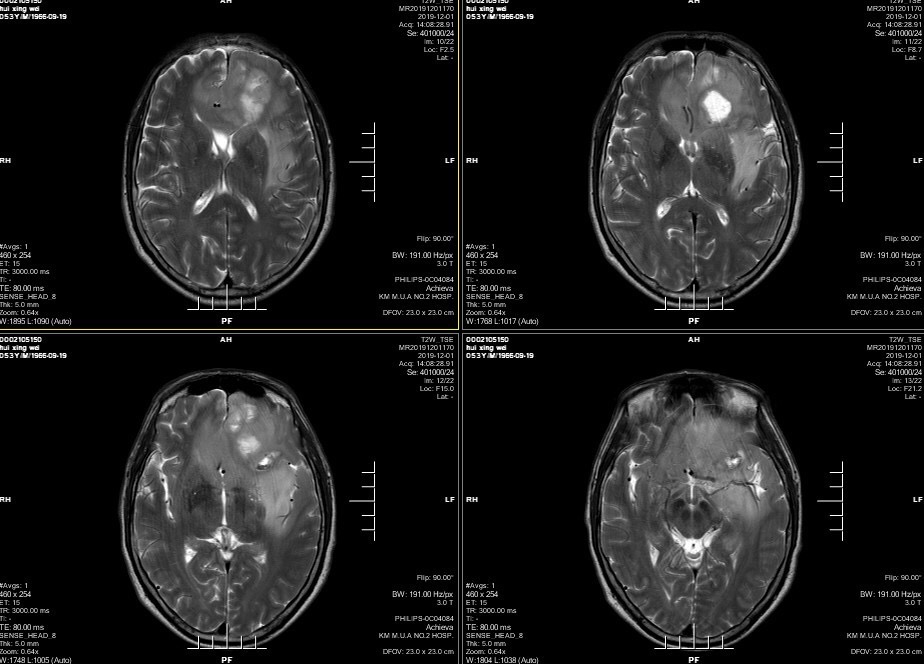

男性患者,53岁,主诉:反复头痛伴恶心一周,突发意识丧失一次。入院查体:神经体统无阳性体征。入院头颅MRI:左额叶胼胝体区囊实性占位,不均匀强化,考虑高级别胶质瘤;长程视频脑电监测提示左侧中央区、顶区、后颞区见中等量低-中-高波幅痫样放电。术前诊断:1.左额叶胼胝体区占位病变;2.继发性癫痫,入院给予降颅压及抗癫痫处理,积极完善术前准备后于2019年12月3日全麻下完成手术,术中行B超引导下切除肿瘤。术后患者无肢体功能及语言功能障碍,复查头颅核磁肿瘤全切,一周后出院开始放化疗治疗。

肿瘤为囊实性。

双侧大脑前动脉受肿瘤推挤。

增强后不均匀强化。